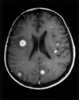

Immune thrombocytopenic purpura (ITP), also known as idiopathic thrombocytopenic purpura or immune thrombocytopenia, is a type of thrombocytopenic purpura defined as an isolated low platelet count with a normal bone marrow in the absence of other causes of low platelets. It causes a characteristic red or purple bruise-like rash and an increased tendency to bleed. [Source: Wikipedia ]